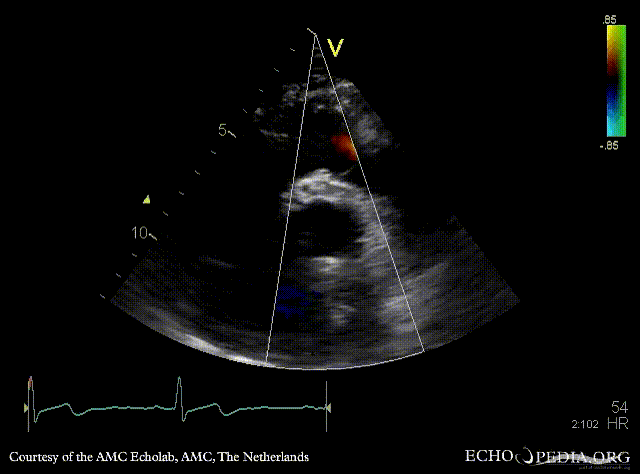

Bentall and aortic valve prosthesis

Courtesy of: AMC Echolab, AMC, The Netherlands

PLAX: aortic valve prosthesis and Bentall in situ PLAX with Color Doppler